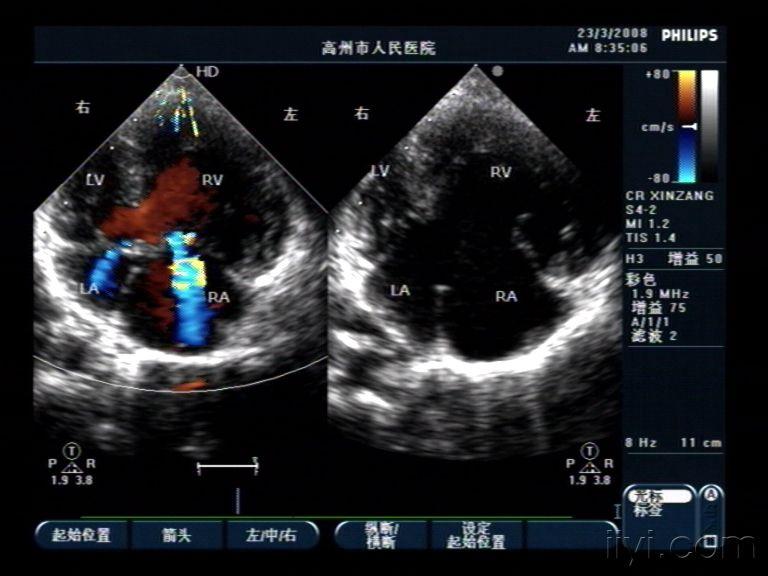

右位心超声,右位心的超声模板

先天性心脏病复合畸形,镜像右位心 超声医学讨论版 爱爱医医学

右位心的超声模板

镜面右位心的超声模板

镜面右位心

超声心动

超声心动图